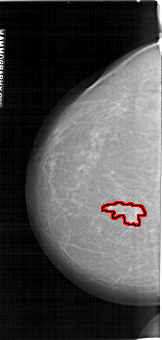

A_1132_1.LEFT_CC

LEFT_CC LINES 6451 PIXELS_PER_LINE 3061 BITS_PER_PIXEL 12 RESOLUTION 43.5 OVERLAY

FILE: A_1132_1.LEFT_CC.OVERLAY

TOTAL_ABNORMALITIES 1

ABNORMALITY 1

LESION_TYPE MASS SHAPE IRREGULAR MARGINS ILL_DEFINED

ASSESSMENT 4

SUBTLETY 5

PATHOLOGY MALIGNANT

TOTAL_OUTLINES 1

BOUNDARY